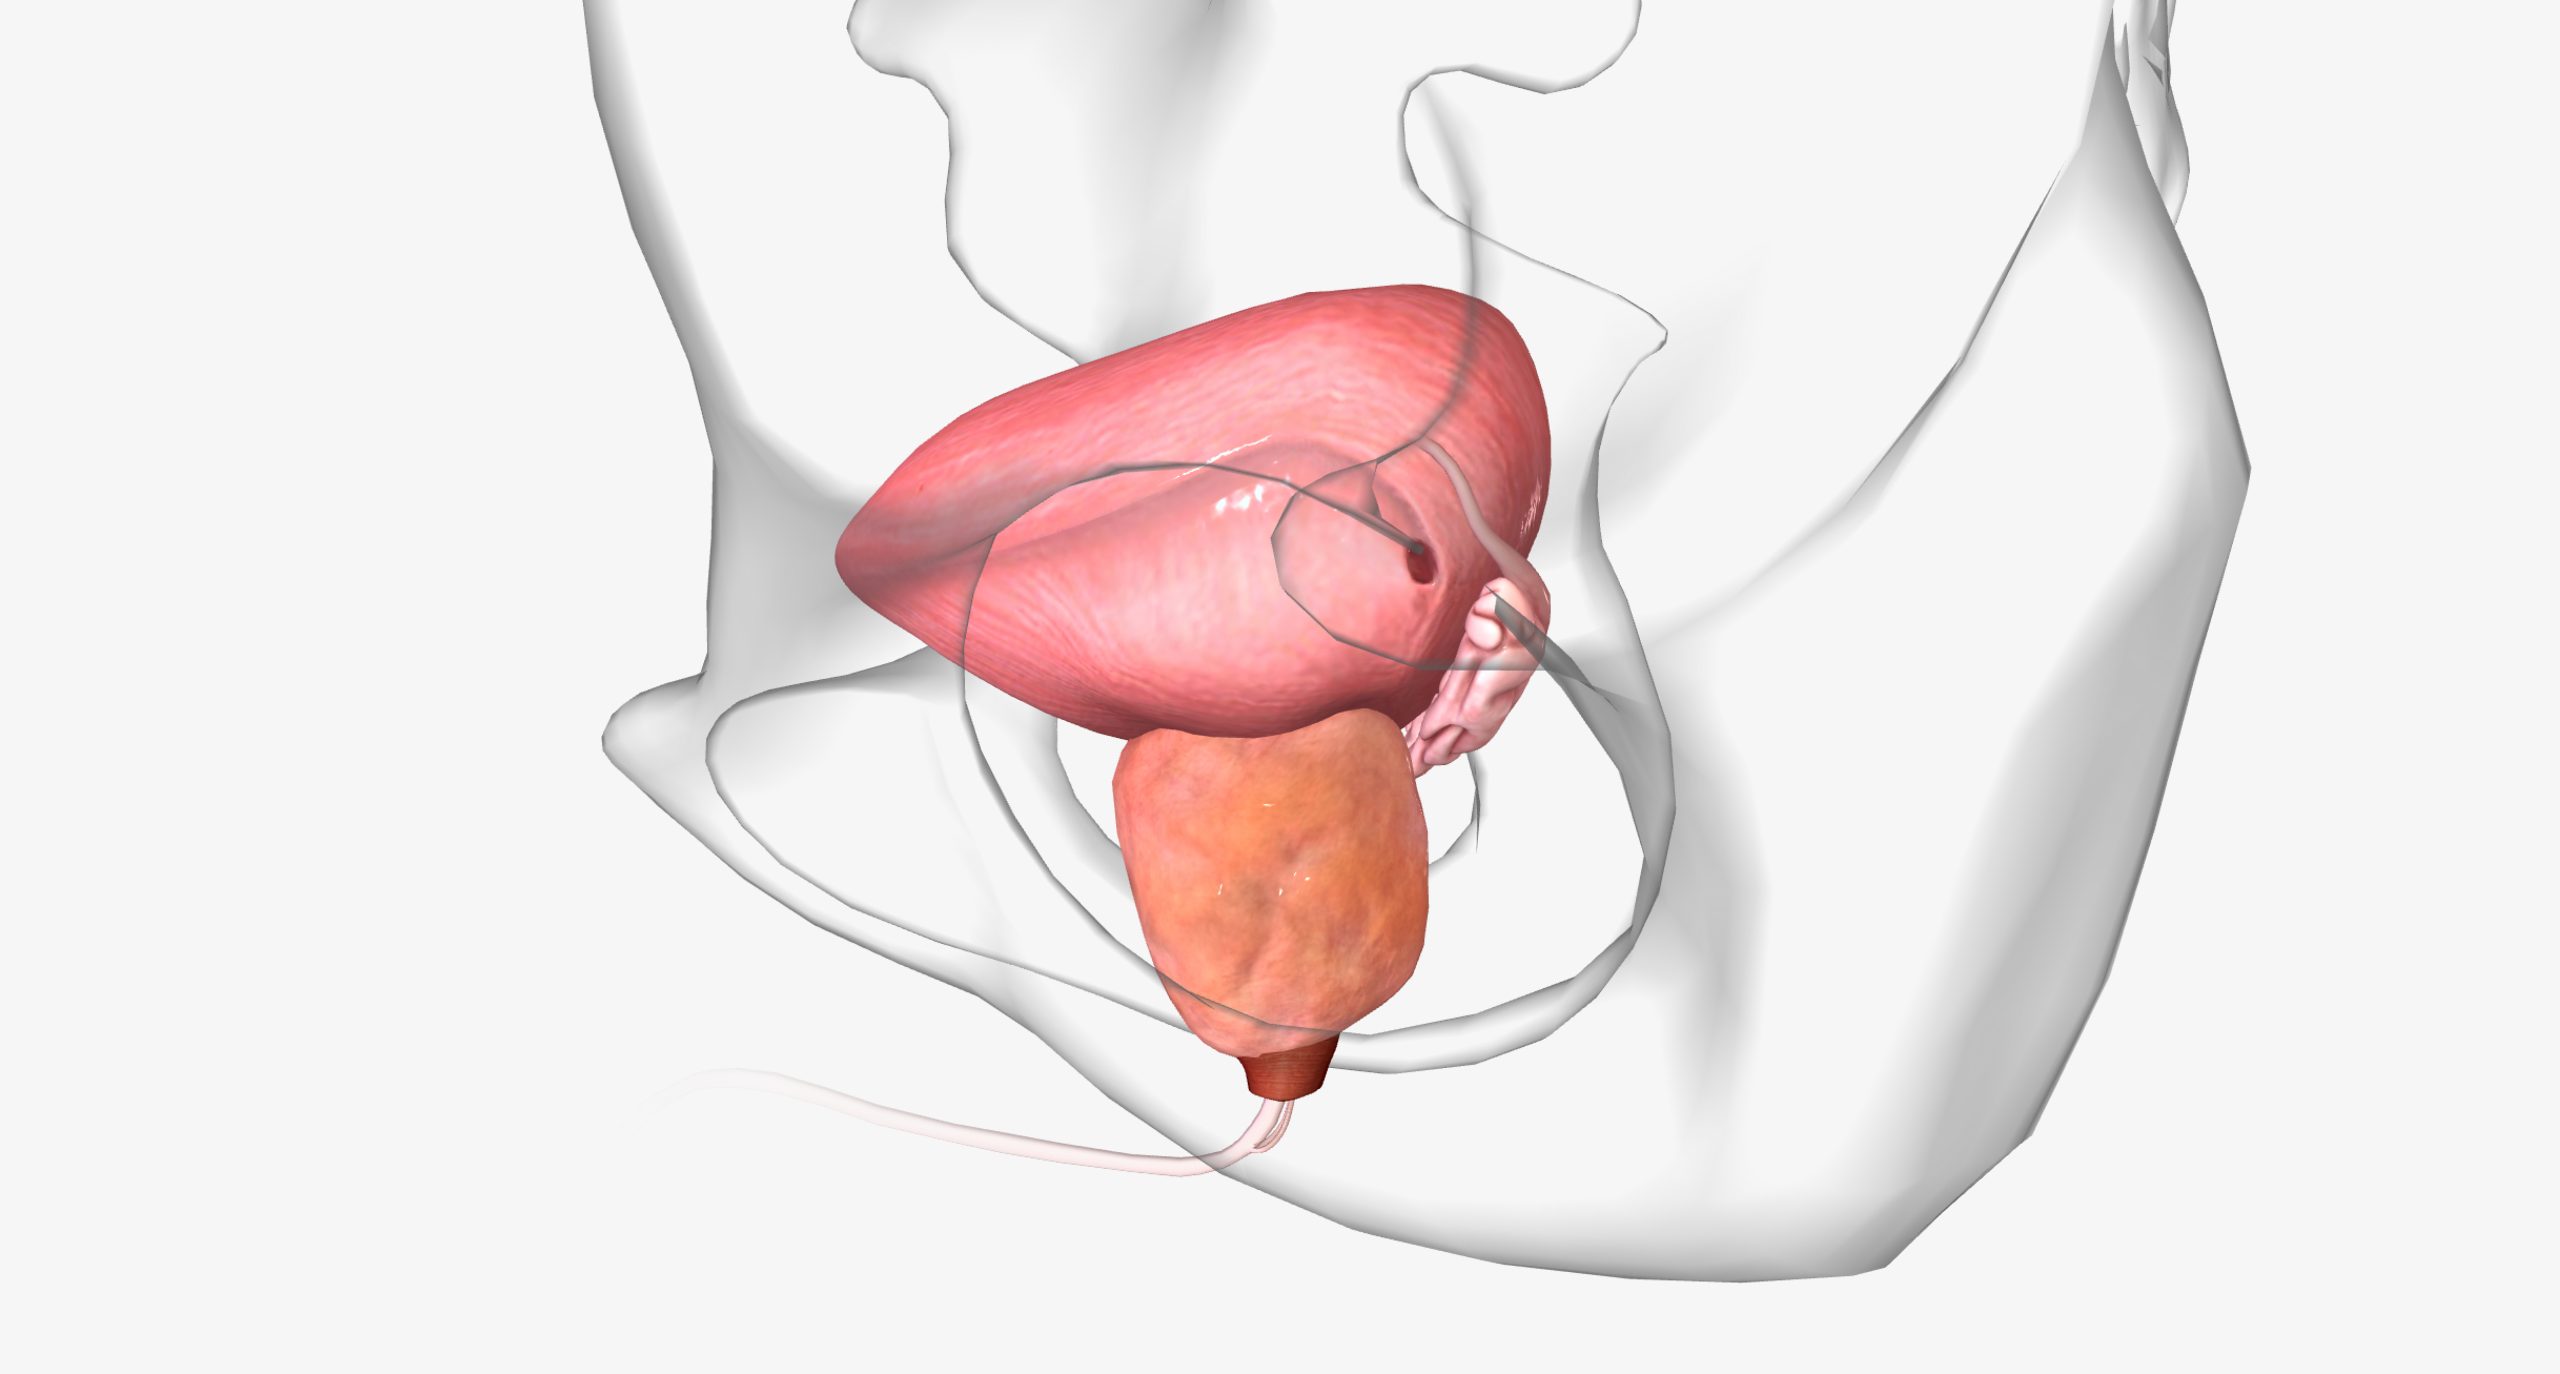

Biópsia de próstata: único exame que confirma o câncer com segurança

A biópsia de próstata é indicada sempre que exames iniciais sugerem anormalidades na glândula. Isso inclui PSA elevado, alterações no…

Biópsia de próstata: exame essencial para detectar o câncer com precisão

A biópsia da próstata é recomendada quando há suspeitas levantadas por exames como o PSA e o toque retal. O…

PSA alto e toque alterado: quando é hora de fazer biópsia de próstata?

A biópsia de próstata costuma ser recomendada quando exames preliminares, como PSA e toque retal, mostram alterações suspeitas. Porém, nem…